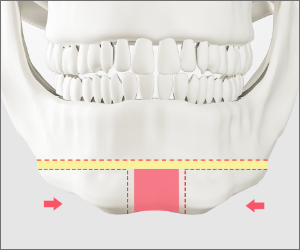

CASE 01

T절골

수술 방법

입안 절개

CT정밀검사로 턱 뼈와

신경선 파악 후 입안 절개

뼈 절제

중간의 턱 끝 뼈를

함께 절제

뼈 고정

나머지 절제된

뼈를 고정

이차각 정리

이차각을 정리하여

매끄러운 턱라인 완성

check-point

Check Point!

환자의 뼈 상태에 따라 노란색 부분의

뼈를 빼내어 높이를 줄일 수 있습니다.